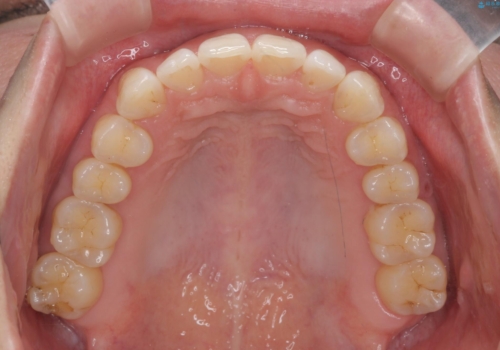

マイクロインプラントを併用することでしっかりとマウスピース全体を後方へ引き、前歯の突出感を改善することができました。

- 前歯の突出感、出っ歯の治療を希望され来院されました。

- 1年10ヶ月